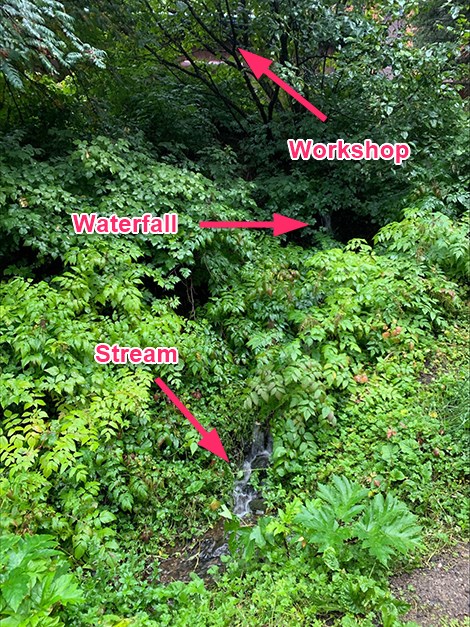

FINDINGS:

Bones:

Coronal oblique fracture of the

distal fibula-mid lateral malleolus is present.

There is a 5 mm lateral shift. Sclerotic line

related to a fracture or arthrodesis of the posterior

quarter of the calcaneus. A repair screw traverses

through the posterior aspect of the calcaneus

towards the talus. Minimal osteophyte of the achilles

insertion.

Joints:

There is widening of the medial

malleolus-talus joint space. Mid-dorsal osteophytic

change at the tarsometatarsal joint.

Soft Tissues:

Moderate lateral and minimal

medial soft tissue swelling at the ankle.

IMPRESSION:

- Helical osteophyte

- Status post repair arthrodesis of the posterior

calcaneus

- Fibular/lateral malleolar fracture with slight

widening of the medial ankle joint

- Dorsal mid foot mild degenerative osteophytes